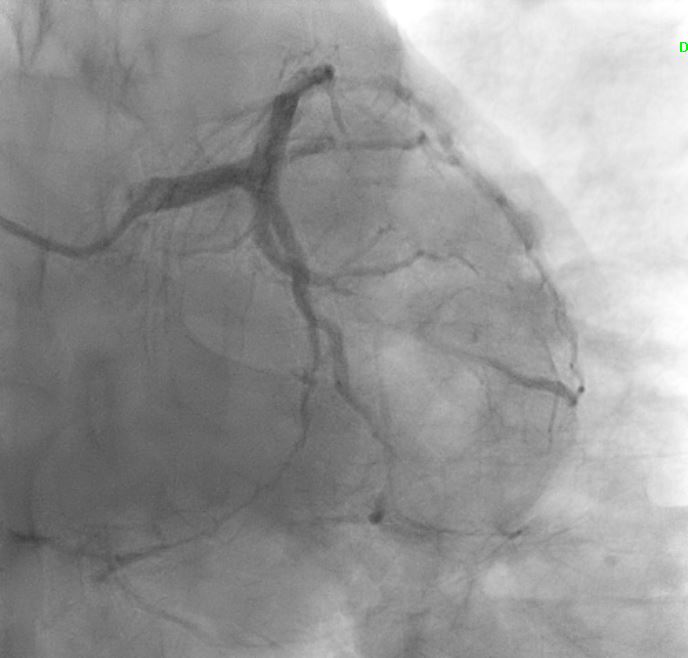

Angiographic assessment showed a normal left main stem, with severe proximal LAD disease exhibiting moderate calcification and providing retrograde collateral supply to both RCA and LCx. The LCx demonstrated severe mid-segment disease with subtotal occlusion of the obtuse marginal 1 (OM1) branch. The RCA showed severe proximal disease and total occlusion of the posterolateral(PL) branch.

Initial engagement with a JR3.5/6Fr guiding catheter provided suboptimal support; this was switched to a SAL 0.75/6Fr guide, which offered only modest improvement. Lesion predilatation was performed with non-compliant balloons (0.85/15 mm and 1.5/15 mm) assisted by a guide extension catheter. Intravascular ultrasound (IVUS)revealed a distal reference vessel diameter of 3.0 mm and proximal reference of 3.5 mm, with evidence of white thrombus at the mid RCA. Further lesion preparation was performed using Naviscore balloons (3.0/15 mm distally and 3.5/15 mm proximally),achieving satisfactory luminal gain. A repeat IVUS run confirmed resolution of the white thrombus. Based on this, a drug-coated balloon(DCB)-only strategy was chosen. EssentialPro DCBs (2.0/40 mm for distal-mid segment, and 3.5/40 mm for mid-proximal segment) were successfully delivered and deployed. Post-procedure IVUS demonstrated significant improvement in minimum lumen area (MLA)—from 2.91 mm©÷to 4.07 mm©÷ (distal) and 1.60mm©÷ to 6.93 mm©÷ (proximal).